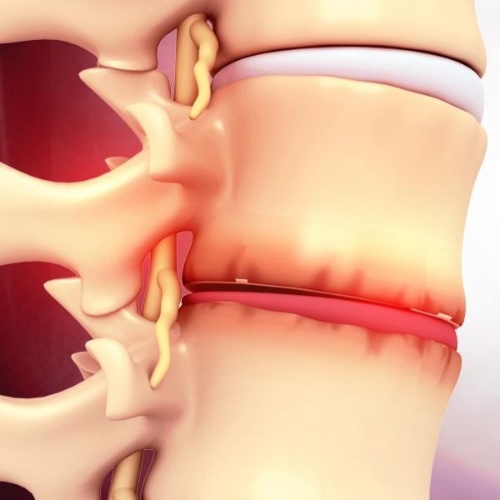

What conditions require endoscopic spine surgery?

Endoscopic spine surgery is ideal for herniated discs, nerve compression, and spinal stenosis. It involves smaller incisions, less pain, and quicker recovery compared to traditional spinal surgeries.